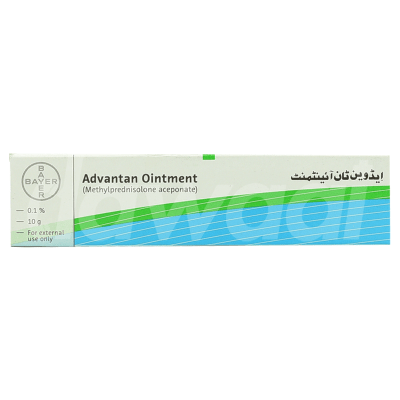

Bayer Pakistan